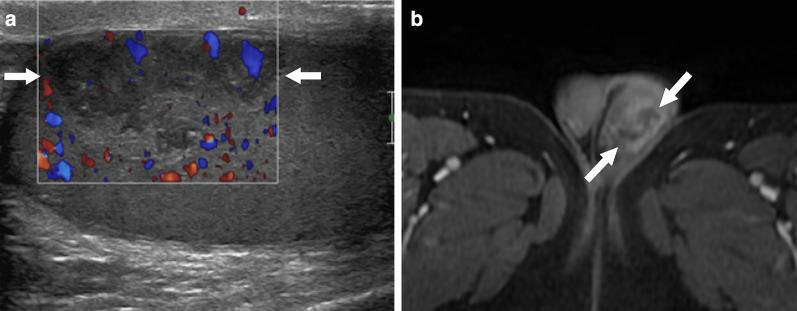

Identifying the deceiver: the non-neoplastic mimickers of genital system neoplasms.

Tumors of the genital system are common and imaging is of crucial importance for their detection and diagnosis. Several non-neoplastic diseases may mimic these tumors and differential diagnosis may be difficult in certain cases. Misdiagnosing non-neoplastic diseases as tumor may prompt unnecessary medical treatment or surgical interventions. In this article, we aimed to present the imaging characteristics of non-neoplastic diseases of the male and female genital systems that may mimic neoplastic processes. Increasing awareness of the imaging specialists to these entities may have a severe positive impact on the management of these patients.